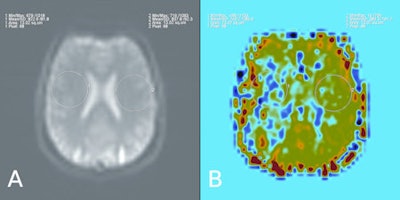

MRI has the advantage of performing a contrast agent-free perfusion study using arterial spin labeling (ASL). ASL describes a group of MR techniques that allow noninvasive perfusion imaging, i.e. without the application of an exogenous contrast agent. Blood water is labeled (by saturation or inversion) as it passes through a magnetic field gradient. As the labeled spins flow into the imaging slice, the tissue magnetization is altered and perfusion-weighted images may be generated, he explained.

ASL has found application in many research and clinical areas. One area that has received much attention is in the evaluation of patients with cerebrovascular disease, both in the initial assessment of perfusion as well as in evaluating treatment response. Vymazal believes the greatest limitation of these techniques may be that MRI is often not the preferred investigative method in acute situations. In non-emergency settings, however, ASL has the benefit of not only being a powerful, noninvasive perfusion imaging method, but also that it allows the investigative physician access to the many other high quality soft-tissue imaging techniques that can be applied in the MRI setting.